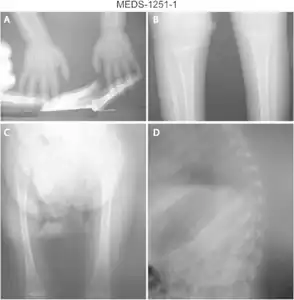

a) Osteopenia in carpal, metacarpal and phalanges b) tibia and fibula with metaphyseal widening/osteopenia c)severe osteopenia d) osteopenic ribs. -